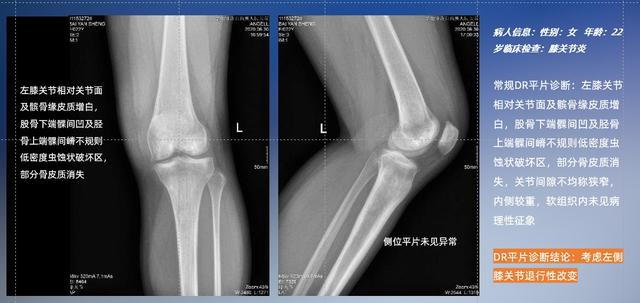

以膝关节疾病检查为例,膝关节在解剖学意义上是一种较为复杂的最大关节,由胫骨上端、股骨下端及髌骨组成。在股骨与胫骨的关节面之间存在两块半月板,分别处于内侧、外侧。膝关节的运动主要为伸、屈,在半屈位时可进行小幅度的旋外、旋内运动。随着现代人们体育生活以及肥胖的增加,膝关节疾病出现高发趋势,特别是关节磨损、膝关节炎与骨关节炎等关节退行性改变,长时间的内翻负荷会造成内侧关节软骨、骨性关节面的磨损。目前针对此类疾病的检查主要为平片下的负重位检查、CT检查以及MRI检查,相较于非负重位检查,负重位检查能更加真实反映膝关节结构中胫骨、股骨、髌骨实际对位关系和关节面的形态特征及关节间隙大小,对膝关节骨关节病诊断准确率高。

普通平片扫描与WR-3D扫描前后诊断结果对比

与此同时,数字化X线摄影技术相较于CTMRI来说,能快速获取真实、直观、满足临床需要的影像。DR的图像具有图像层次丰富、空间分辨力高、影像边缘锐利清晰、密度分辨力高级细微结构表现出色等特点,针对膝关节解剖结构数字化X线摄影技术应用价值很高,尤其是是对骨小梁与骨皮质的显示非常清楚。在负重位状态下,数字化X线三维摄影扫描与重建,能够更好的呈现受检者关节受力改变的状态。亿万28入口网页版-亿万28网页在线玩-万28官网下载最新版-亿万e网址pg-亿万28pg电子-亿万28赏金女王-亿万28娱乐科技创新的WR-3D动态三维数字化X线摄影技术,通过数字化X线摄影完成三维扫描并重建三维影像信息,包括MPR多平面重建、MIP重建以及VR绘制。扫描时间短,剂量相较于CT设备大幅缩减,同时成本更低,在临床诊断以及医疗方案制定中具有极大的价值意义。相较于普通平片下的负重位扫描,负重位动态三维扫描摄影技术能够避免二维状态下的组织结构重叠、密度分辨率不足、组织解剖结构难以分辨等问题,WR-3D支持多角度的动态三维摄影观察,能全面的呈现被检查部位在多个角度下三维影像信息,极大的减少了二维负重位检查的漏诊率。